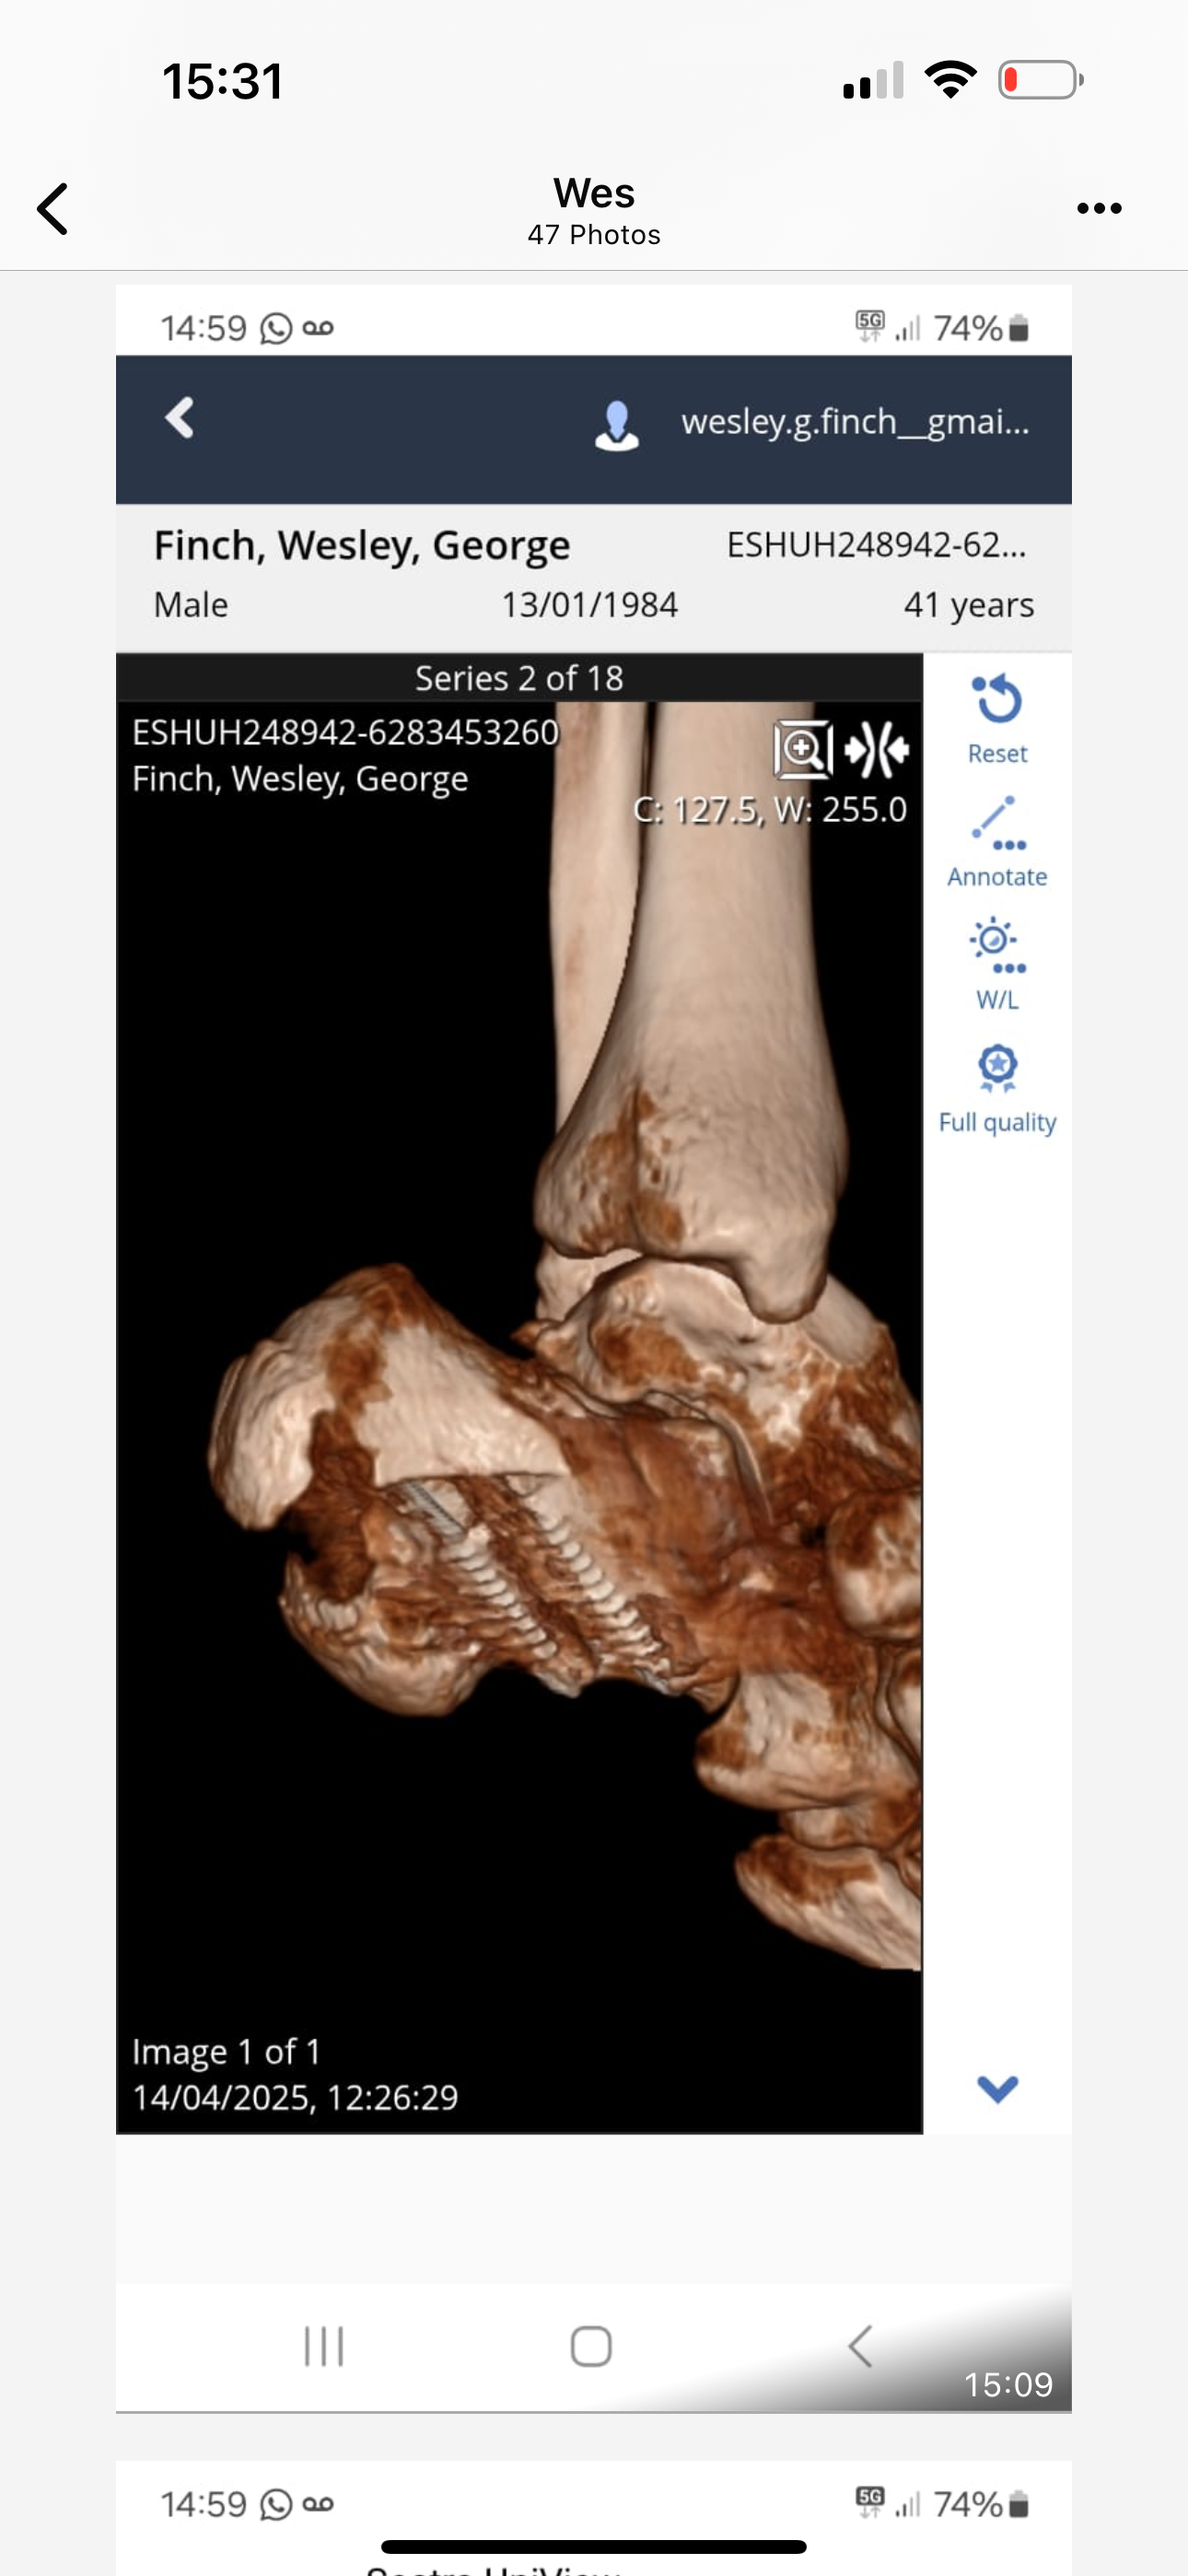

The first surgery was a complete failure and the CT scan on 14/04 showed catastrophic breakdown of bone, tissue and tendons. His Achilles tendon was completely obliterated. The NHS doctors failed to tell Wes any of this and just told him the surgery needed to be repeated as it had failed. The scan showed severe Osteomyelitis and tissue infection, which turned out to be MRSA which is very hard to cure. The osteomyelitis can also simmer for YEARS if not for the rest of his life if he keeps his foot. At this point, amputation is inevitable the way things are going. The doctors failed to give him antibiotics after his first surgery which went completely against NHS guidelines. They also went against their “Duty of Candour” as doctors.

I apologise in advance for images that I will share in the updates. I can’t really make people understand how horrific this all is without showing you these images. I will also share scans and explain what they show.